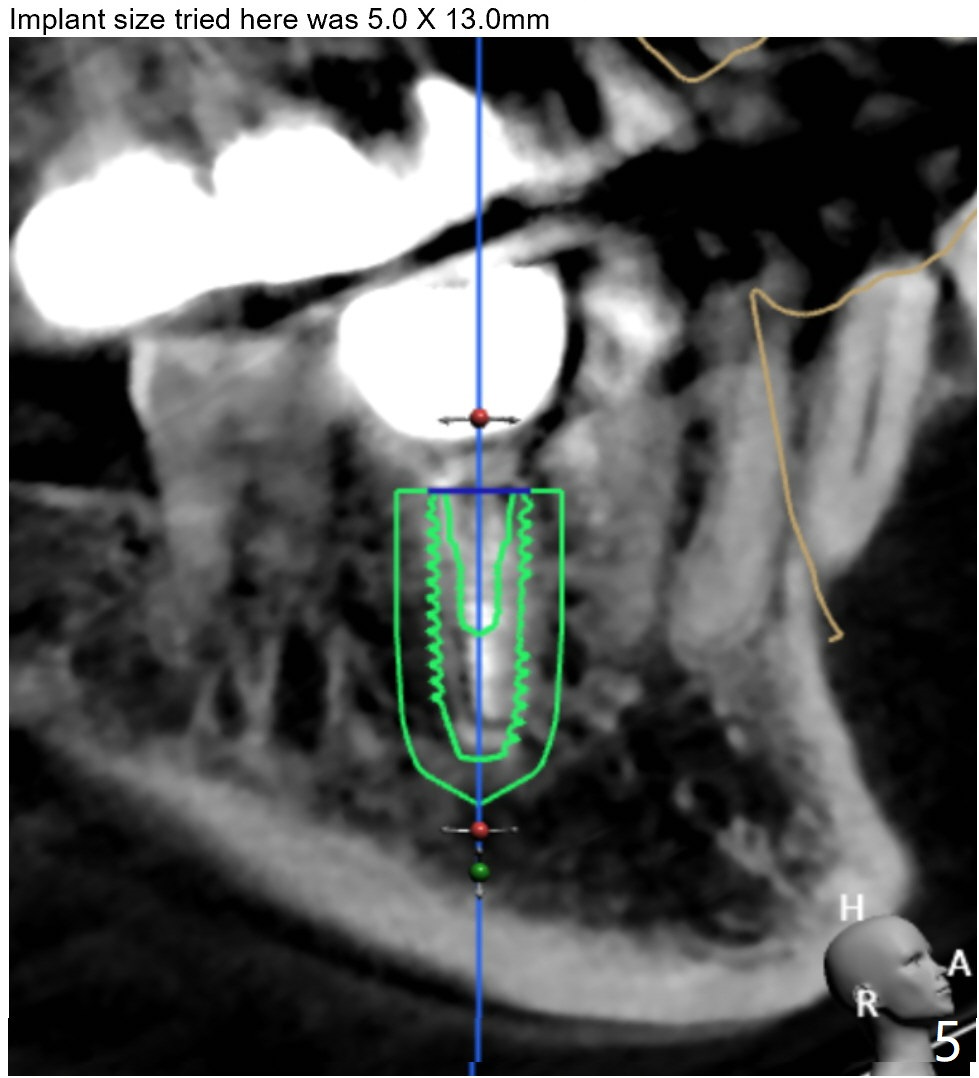

Twenty six months post cementation, periimplantitis develops buccally at #30 (Fig.1) due to buccal (B) placement (Fig.2) with buccal thread exposure (red line), as compared to the same sized implant at #19 (Fig.3). After removal of the crown and abutment and incision, use Titanium brush to clean the exposed threads. Following implant removal and removal of the lingual bone, place the same implant lingually (Fig.4 arrow) with the used-to-be-exposed surface facing lingual (Fig.4 red line). The buccal gap will be filled with autogenous bone harvested lingually and allograft. Use 2-3 pieces of PRF membranes to close the wound, i.e., to bury the implant. A 5x13 mm implant (Fig.5) placed lingually (Fig.6 L) appears to be unable to gain more than .77 mm native bone (Fig.7). Lab declines to make a guide.